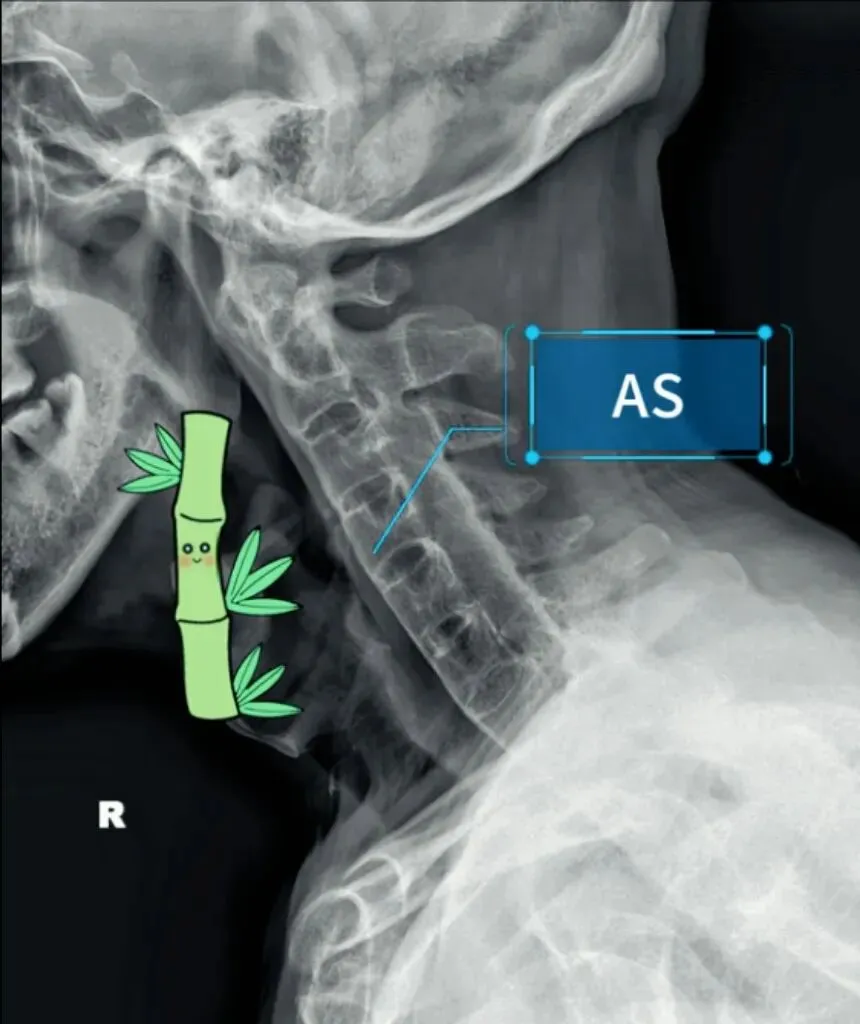

二弓指的是颈椎生理曲度,在颈椎侧位X线片中,正常生理状态下呈现向前凸出的弧形曲线,呈半C型前凸类似弓形,是人体脊柱生理曲度的重要组成部分。颈椎曲度变化能够反映颈椎整体功能的变化。

常见的颈椎曲度改变有曲度变直和曲度反曲。

颈椎生理曲度测量的方法多种多样,其中应用最广泛的测量方法是Borden法。从齿状突后上缘开始向下将每个椎体后缘相连成为一条弧线,然后从齿状突后上缘至C7椎体后下缘作一直线测量,两条线间最宽处的垂直横交线的距离即为颈椎生理曲度深度。

正常时,最宽处在C4椎体水平正常为12毫米,正负5毫米,小于7毫米为生理曲度变直,大于17毫米为生理曲度过度前屈,小于零时为生理曲度反曲。